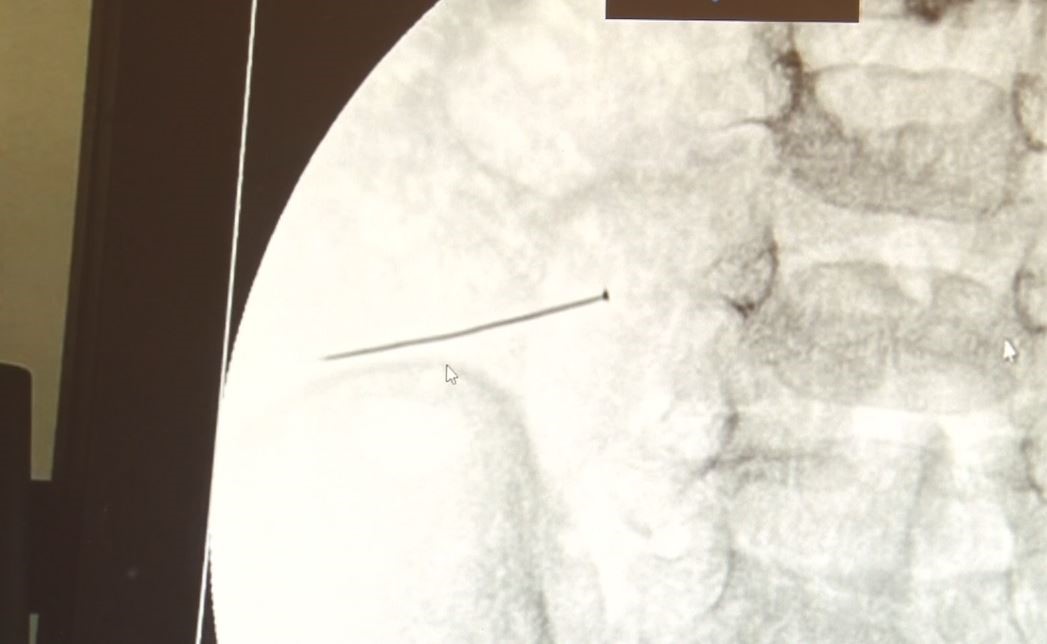

Öte yandan, yaklaşık 3 santimlik toplu iğne filme yansıyan görüntüsüyle gözler önüne serildi.